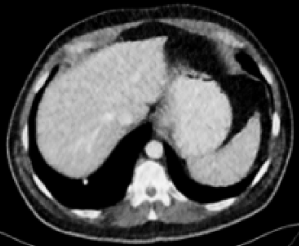

Figs. 3 and 4 demonstrate precise removal of noise from whole scans as well as specific regions of interest (ROIs), proving the effectiveness of our model over baseline architectures and other self-supervised tasks. As shown, both the RVAE and SSWL are able to quantitatively and qualitatively outperform their respective counterparts.